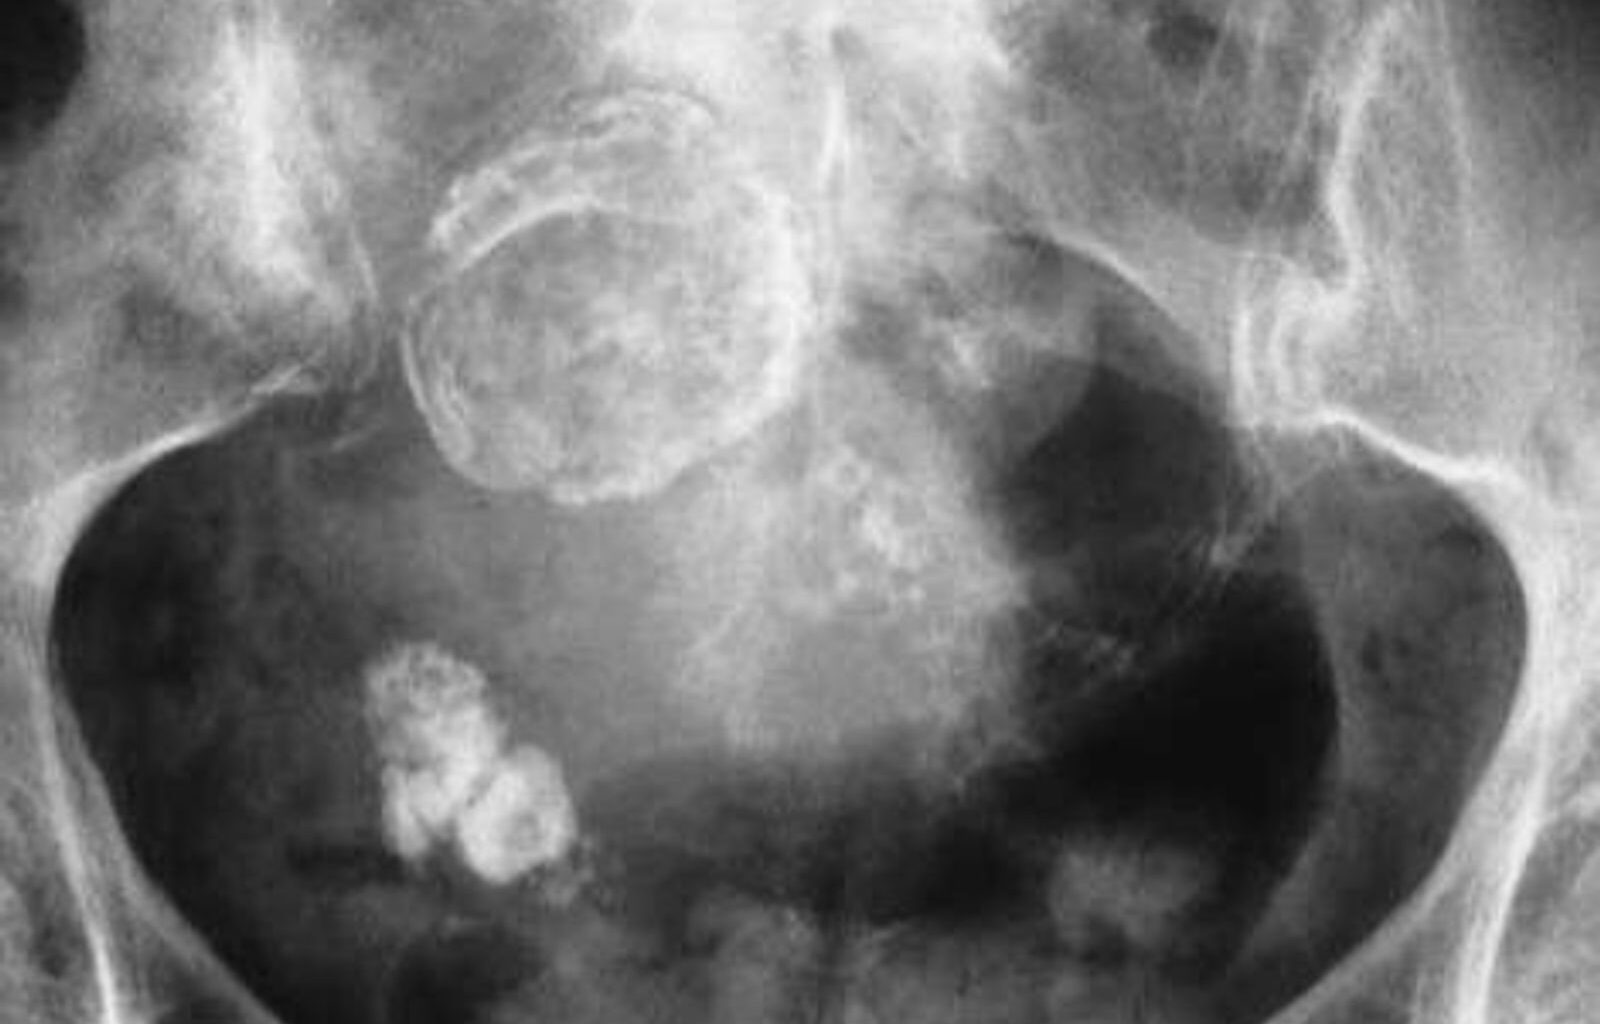

Les experts estiment qu’entre 6 et 20 % des femmes sont affectées par le SOPK qui provoque des symptômes allant d’une augmentation de la pilosité sur le visage et le corps à l’infertilité. Pour être diagnostiquées, les femmes doivent présenter deux des trois symptômes suivants : règles irrégulières et peu fréquentes, à savoir huit fois par an ou moins ; des taux élevés d’androgènes, hormones mâles comme la testostérone ; et des follicules ovariens immatures, souvent appelés kystes, visibles à l’échographie.